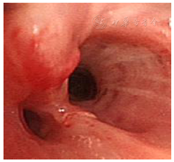

纤维支气管镜检查:气管正常,隆突锐利,左上叶舌段支气管黏膜充血、水肿、肥厚,局部结节状新生物见图1。余双侧主支气管及各叶、段支气管黏膜均无充血、水肿,管腔通畅无狭窄。